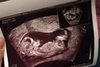

Chyba noga przysłania wyrostek [emoji6]Hej dziewczynyjak myślicie chłopczyk czy dziewczynka?

Hej dziewczynyjak myślicie chłopczyk czy dziewczynka?

O jeju, ja tak patrzę na to zdjęcie i nic nie widzę ale jak "jajeczka" to bardzo dobrze!Widzę jajeczka?![]()

Tak, i do tej pory nie chce pokazać co tam ma. Obecnie 17 tydzieńJeśli dobrze widzę to zdjęcie z 12 tyg.?

Jak byłam na usg 16/17 tc to dr wciąż nie chciała potwierdzać na 100% bo nie było dokładnie jeszcze widać.Tak, i do tej pory nie chce pokazać co tam ma. Obecnie 17 tydzień![]()

No to jak 12 to nie ma czego szukać. Wyrostka też nie widać.Tak, i do tej pory nie chce pokazać co tam ma. Obecnie 17 tydzień![]()